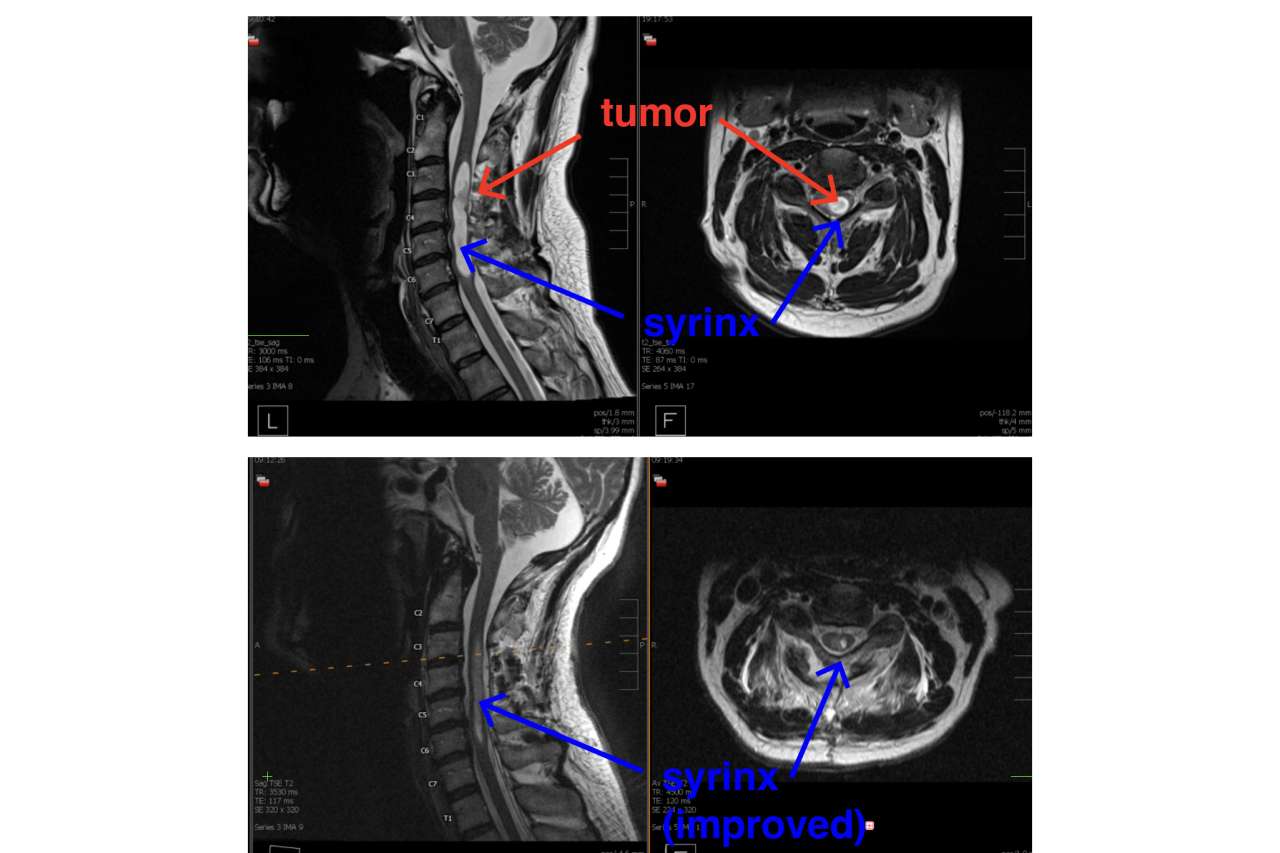

Before and after MRI of spinal tumor removal

MRIs of the spine before and after the tumor removal. (UCLA Health Neurosurgery)

After ordering additional MRIs of Daniels’ entire spine, Dr. Vivas diagnosed him with a rare spinal tumor. The hemangioblastoma, having formed spontaneously, was slowly growing in the blood vessels of the neck’s cervical spine. It was likely benign, and unlike a malignant tumor, wouldn’t move or grow to other areas.

However, the tumor was blocking the flow of spinal fluid, which accumulated and caused a syrinx.

Dr. Vivas explained that the syrinx would likely expand over time and progressively cause paralysis of his arms and legs. The appointment not only convinced Daniels to undergo surgery but also built his trust in the doctor.